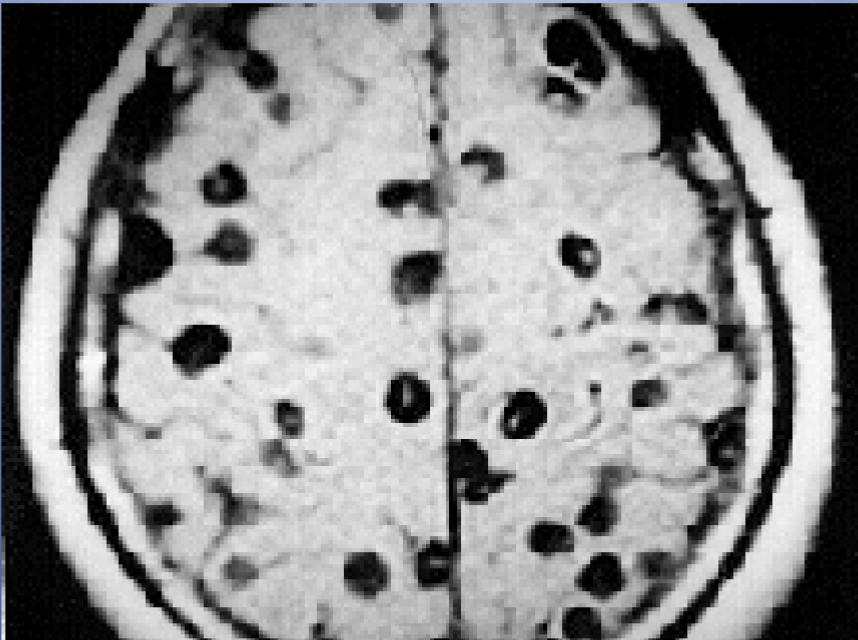

Cysticercosis

MRI shows numerous tapeworm larvae (dark, hole-like objects) in a human brain